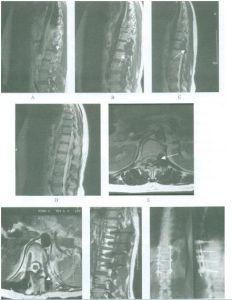

3、MRI檢查多數惡性纖維組織細胞瘤的邊界清楚,少數呈侵潤性生長,邊界不清楚,腫瘤呈結節狀,可有分葉。在T1加權像為低或中等信號,T2加權像呈高信號,注射Gd-DTPA增強後,腫瘤內不均勻強化。

BMFH由於缺乏特殊的影像學表現,故不能根據術前X線片、CT、MRI明確診斷,但影像學檢查可以幫助診斷,並且對確定手術方案有很大幫助。根據本組資料,作者總結BMFH影像學表現:(1)X線表現:BMFH的X線表現多種多樣,特徵性少。以蟲噬狀、斑片狀或大片狀溶骨性破壞為主,邊界不清,少數可有邊緣硬化,常伴有軟組織腫塊,骨膜反應無或輕微,這是BMFH的重要特點。(2)CT表現:更清楚地顯示骨質破壞和軟組織腫塊,骨質破壞同X線,少數病灶為囊狀或膨脹性,內有粗條索狀及格線狀嵴,並見邊緣硬化,類似良性病變,骨膜反應少見。(3)MRI表現:BMFH的MRI表現缺乏特異性,但其對腫瘤髓內侵犯、周圍邊界可清楚顯示,指導手術切除範圍,還可顯示腫瘤與鄰近血管的關係以及判斷腫瘤術後改變與術後復發等方面優於X線及CT。